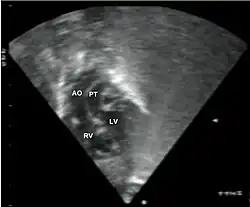

Subcostal echocardiographic view showing discordant ventriculoarterial connections together with the presence of parallel, rather than crossing, great arteries arising from the ventricles.